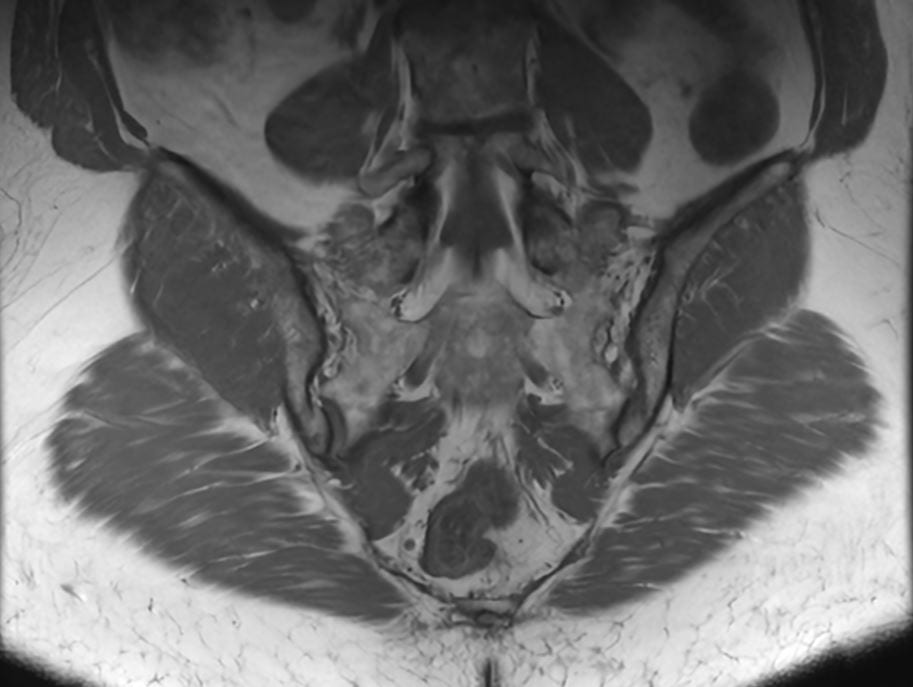

Få præcis diagnose af dine SI-ledsmerter med avanceret MR-scanning hos Progardia. Vores kraftfulde 3 tesla scanner giver ekstraordinært detaljerede billeder af sacroiliacaleddet, hvor rygsøjlen møder bækkenet. Oplev markedets mest nøjagtige visualisering af inflammation, artrit og andre forandringer, der ofte overses ved konventionelle undersøgelser.

En MR-scanning af SI-led (sacroiliacaled) er en avanceret, smertefri undersøgelse, der giver detaljerede billeder af forbindelsen mellem korsbenet (sacrum) og hoftebenet (ilium).

Vores 3 tesla MR-scanner bruger et kraftigt magnetfelt og radiobølger til at skabe præcise billeder af leddet, omkringliggende knogler, brusk, ledbånd og bløddele – helt uden brug af røntgenstråling.

SI-leddet er et komplekst led, der ofte er svært at undersøge med konventionelle metoder. MR-scanning kan vise tidlige tegn på inflammation, artrit, slidgigt og andre forandringer, der kan være årsag til lænde-, hofte- eller bækkensmerter. Denne undersøgelse er særligt værdifuld ved mistanke om inflammatoriske rygsygdomme som f.eks. ankyloserende spondylitis (Morbus Bechterew).

Eksempler på MR Scanninger